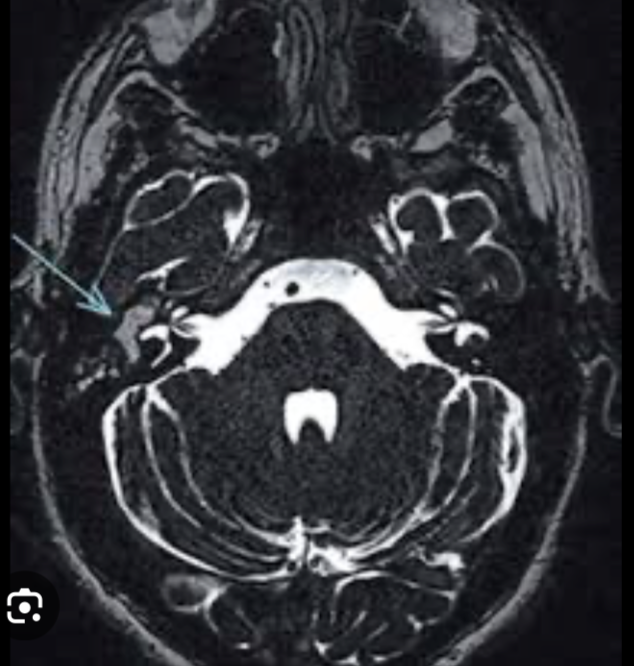

Q

Otitis media en RM